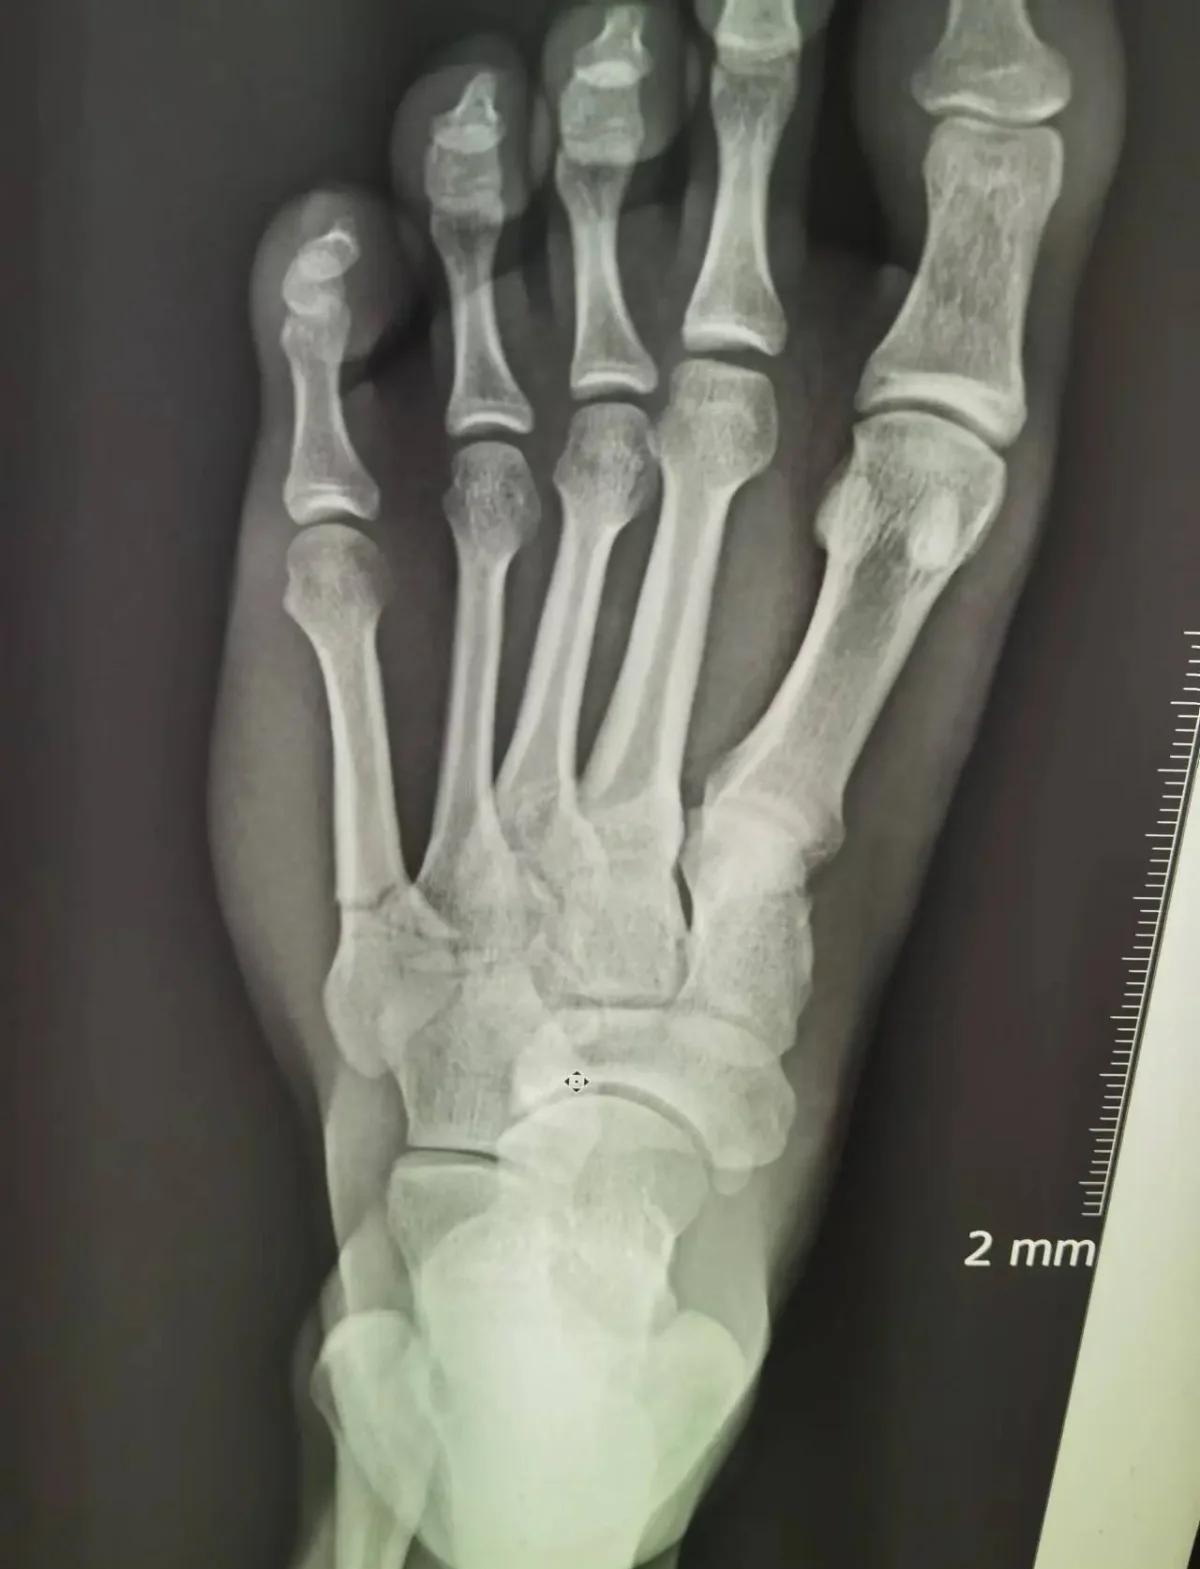

第五跖骨骨折愈合的时间一般是在三个月左右骨折初期首先要拍摄X片,如果第五跖骨骨折对位对线良好,可以使用石膏或支具制动,制动的时间在六周左右在六周的时候可以拍摄X片,如果骨折断端已有连续性骨痂通过,这就代表骨折具备了初始的稳定性,此时可以拆除石膏,在双拐的支撑下逐渐下地,部分负重行走。